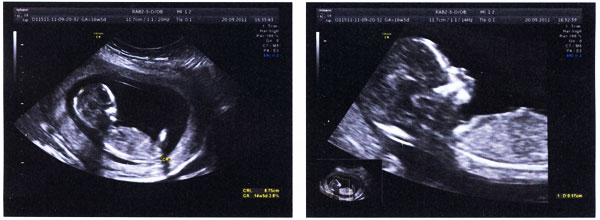

B超检查单,有大图!

(2011/09/20 AM)